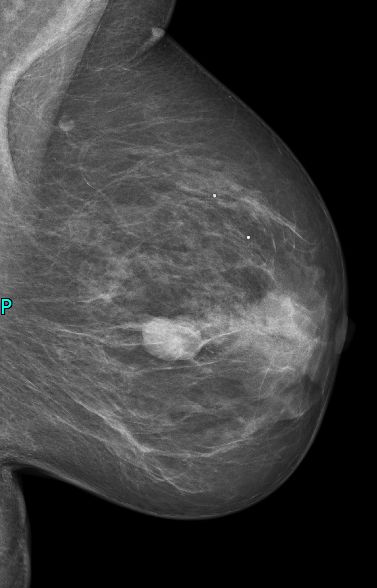

| intrazystisches DCIS | Eine 73-jährige Frau bemerkte in der linken Brust oben innen einen 3cm großen zystischen Tastbefund. Die Mammographie spricht für eine gutartige Zyste. Allerdings ist die Neubildung einer Zyste in dem Alter ungewöhnlich. | ||

![]() |